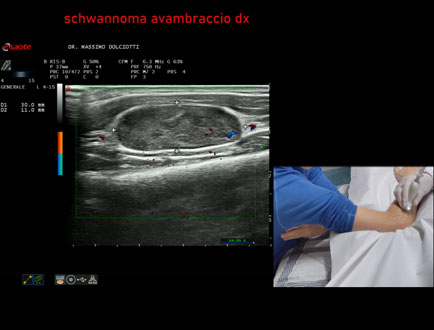

Età Paziente: M 48 anni

Motivazione dell'esame: da circa 1 anno rilievo di tumefazione all'avambraccio destro.

Commento all'esame: le immagini ed il video documentano, all'avambraccio destro, all'interno del muscolo estensore delle dita, formazione ipoecogena a margini definiti, delle dimensioni di 28,5 mm per uno spessore di 12,1 mm, con modesti segni di vascolarizzazione intra nodulare, da ricondurre, come prima ipotesi, a Schwannoma.

Conclusioni: schwannoma all'avambraccio destro (schwannoma of the right forearm).